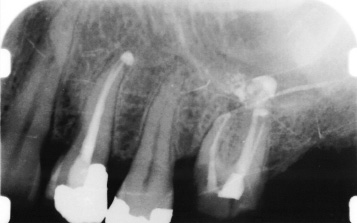

Root Canal Therapy or Endodontic Treatment is used to treat teeth that have been badly decayed or damaged and have consequently caused the pulp inside the tooth to die or become infected.

Root canal treatment is like having a filling inside the tooth all the way down to the root ends. The canals are enlarged, shaped and cleaned from debris and infected pulp. Anti-bacterial and anti-inflammatory medicines may be placed inside the canals during the procedure to help stop the inflammation and infection.